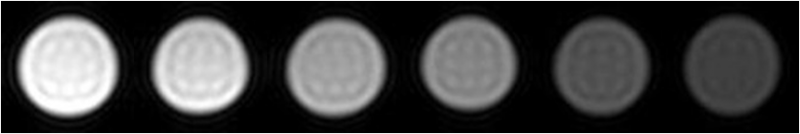

´ÅÐÔÄÉÃ×Á£×ÓÓÃ×÷´Å¹²Õñ³ÉÏñ£¨MRI£©ÔìÓ°¼Á

ÒÔǰֻÊÇÔÚÓ¡ÏóÖУ¬ÎªÁËÕâÊÂÕÒÁËһϣ¬»¹Ã»ÓÐÀ´µÃ¼°ÈÏÕæ¶Á¡£Ï£ÍûÓÐÖú http://www.ema.europa.eu/docs/en ... /01/WC500067464.pdf from wiki: http://en.wikipedia.org/wiki/MRI_contrast_agent Iron oxide: Superparamagnetic[edit] Two types of iron oxide contrast agents exist: superparamagnetic iron oxide (SPIO) and ultrasmall superparamagnetic iron oxide (USPIO). These contrast agents consist of suspended colloids of iron oxide nanoparticles and when injected during imaging reduce the T2 signals of absorbing tissues. SPIO and USPIO contrast agents have been used successfully in some instances for liver tumor enhancement.[17] Although SPIOs and USPIOs have been approved for use in the past, it appears that all of the agents listed below are no longer available with the exception of the oral iron oxide contrast agent, Lumirem/Gastromark. Feridex I.V. (also known as Endorem and ferumoxides). This product was discontinued by AMAG Pharma in November 2008.[18] Resovist (also known as Cliavist). This was approved for the European market in 2001, but production was abandoned in 2009.[19] Sinerem (also known as Combidex). Guerbet withdrew the marketing authorization application for this product in 2007.[20] Lumirem (also known as Gastromark). Gastromark was approved by the FDA in 1996.[21] Clariscan™ (also known as PEG-fero, Feruglose, and NC100150). Development was discontinued due to safety concerns.[22] |